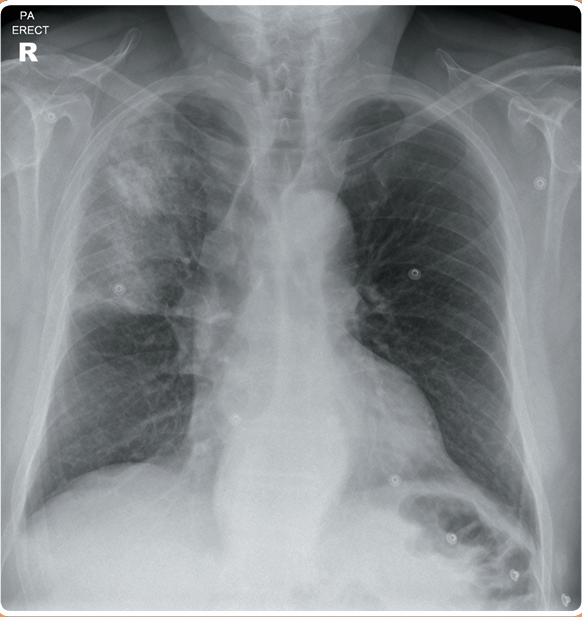

Un hombre de 54 años se presenta a la sala de emergencias con dificultad respiratoria aguda. Tiene antecedentes de enfermedad arterial isquémica y un historial de 20 paquetes-año de tabaquismo. En el examen físico, está afebril, con saturaciones del 90% en aire. La frecuencia cardíaca es de 100 lpm y la frecuencia respiratoria de 22. Se observa matidez y estertores inspiratorios en ambas zonas bajas. La presión yugular está elevada 4 cm. Se realiza una radiografía de tórax para buscar edema pulmonar.

La radiografía muestra características de insuficiencia cardíaca (cardiomegalia, opacificación intersticial, desvío venoso en los lóbulos superiores y pequeños derrames pleurales).

Se deben realizar análisis de electrolitos y función renal (U/Es) para evaluar la función renal, así como un hemograma (FBC) para detectar cualquier anemia asociada. Un electrocardiograma (ECG) sería útil para buscar posibles cambios eléctricos nuevos. Una ecocardiografía (ECHO) permitiría evaluar la función del ventrículo izquierdo.

El paciente debe ser tratado por edema pulmonar agudo/insuficiencia cardíaca. Una radiografía de tórax de seguimiento puede usarse para monitorear la respuesta al tratamiento.